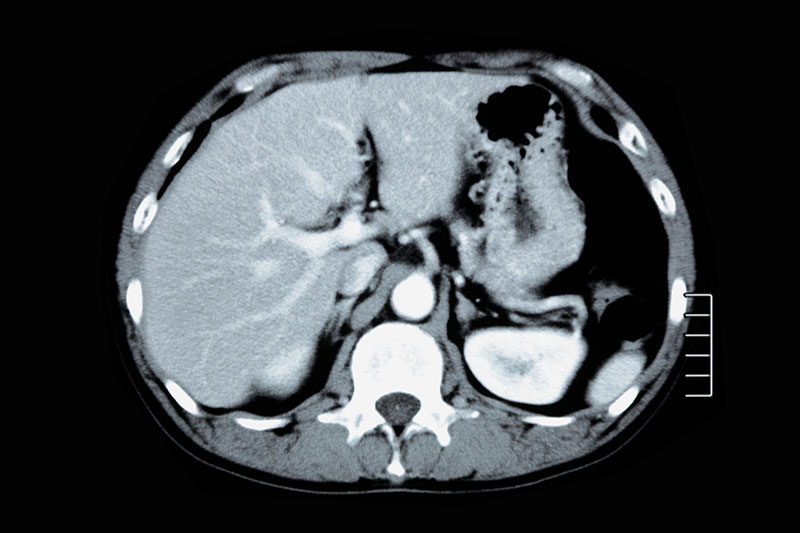

CT検査とは、正式名称を「コンピュータ断層撮影(Computed Tomography)」といい、コンピュータを用いて体の断面を画像化する検査です。

当院で使用している装置は「マルチスライスCT」で、1ミリ単位の細かい間隔で鮮明な断層画像を作成できます。

腹部CT検査では、主に肝臓・胆のう・膵臓・腎臓・脾臓といった腹部の臓器を対象に、腫瘍や結石(胆のう・腎臓・尿管)、脂肪肝、炎症などの有無を確認することができます。

また、腹部超音波ではガスの影響で観察が難しい場合でも、CT検査ならクリアに映し出せることが多く、より正確な診断が可能です 。